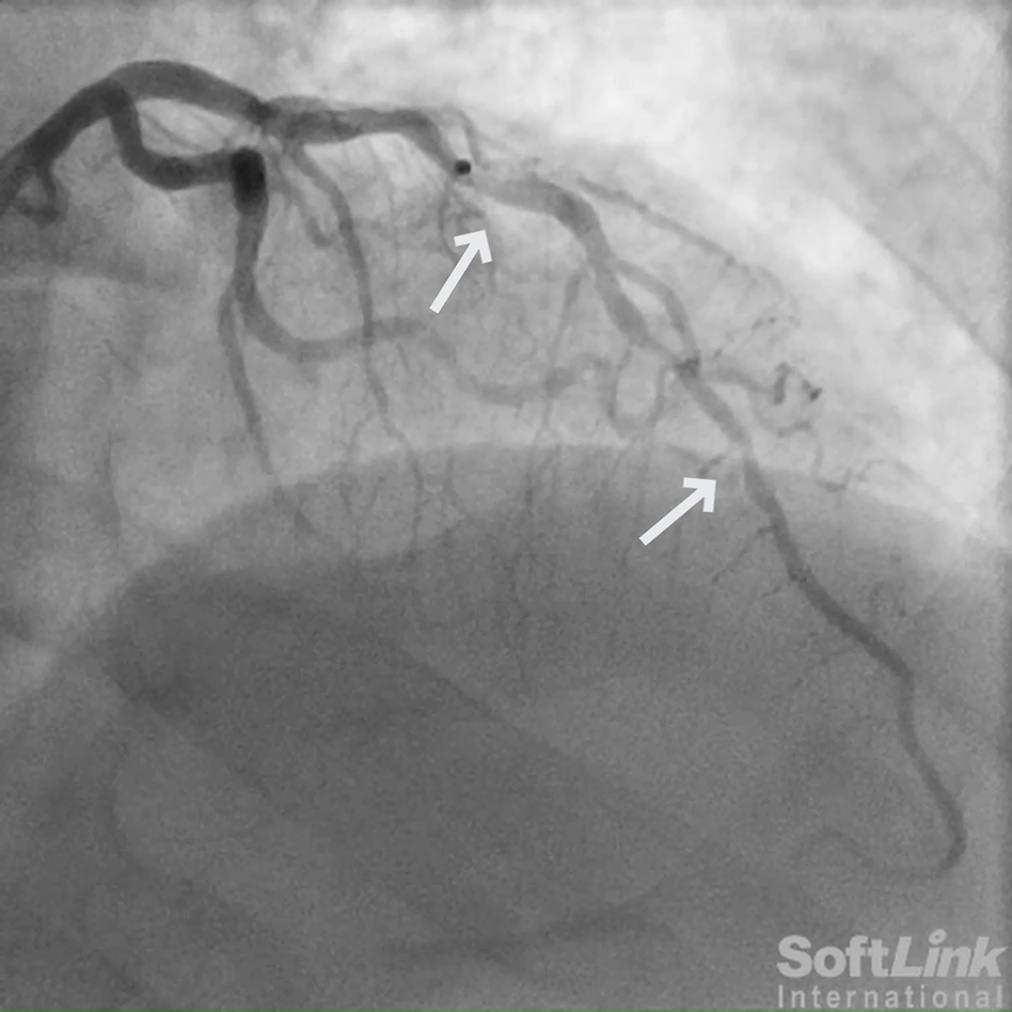

A 73-year-old female with a history of coronary artery bypass grafting (CABG) including LIMA to distal LAD, SVG to D1, and SVG to OM2, presented with recurrent, disabling chest pain.